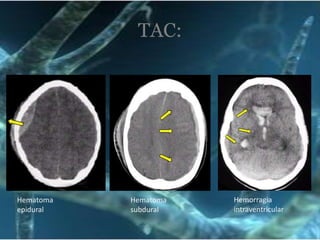

Hemorragia intraventricularHematoma epiduralHematoma subduralTAC:

HemorragiaextraduralesTCESangrado rápido (hematoma)lesión cerebral adicional. PICDX: TAC cerebral y craneal

Solicitar de inmediatoHemorragia intracranealTC de Cráneo simpleHematoma epiduralMuerte en 2 - 4 hrsTC de Cráneo         con ventana óseaFracturas en:Evidencia contusional de trauma cerebralSi la evolución no es la esperadaPaciente en coma y TAC sin mucha evidenciaRM de Cráneo